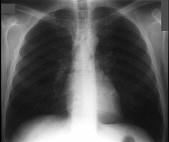

问题 在哮喘急性发作的病程中患者出现颈部皮下气肿,胸片见图。说明此患者有下列哪一种并发症存在 ( )

选项 A.气胸 B.纵隔气肿 C.间质性肺气肿 D.肺囊肿 E.肺大疱

答案 B